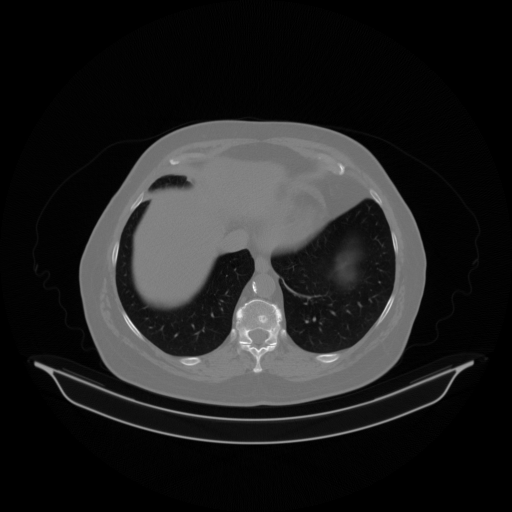

Image Grid

4Γ—3 grid: Rows show different image types (Original NATIVE, Reconstructed NATIVE, Original VENOUS, Generated VENOUS), Columns show windowing techniques (No Window, Lung Window, Mediastinum Window)

Original NATIVE CT scan (input)

Full window (WL 1023.5, WW 4095 β†’ Low βˆ’1024, High +3071)

Actual HU range: [-1024.0, 1049.0]